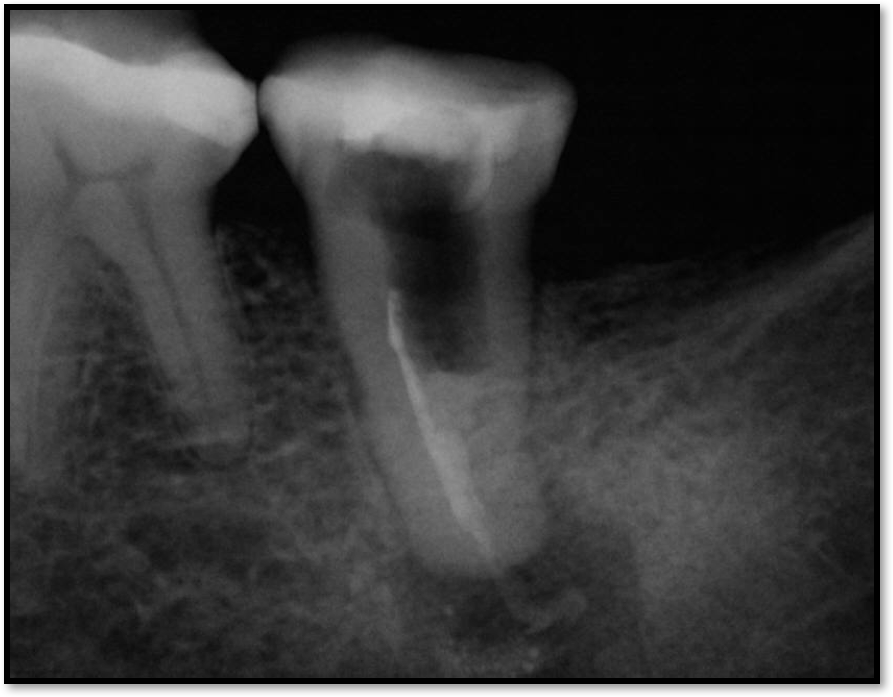

Figure 2 shows a situation where the clinician excavated the tooth of a patient with decay, and it pulped out. The buccal and lingual walls were intact; however, the walls were minimal, and there were still fragments of amalgam and cracks. If the clinician prepared this tooth after building it up, the clinician would lose all the good tooth structure that was left. This tooth would likely need a post.

Fig 2. Minimal walls.

Figure 2